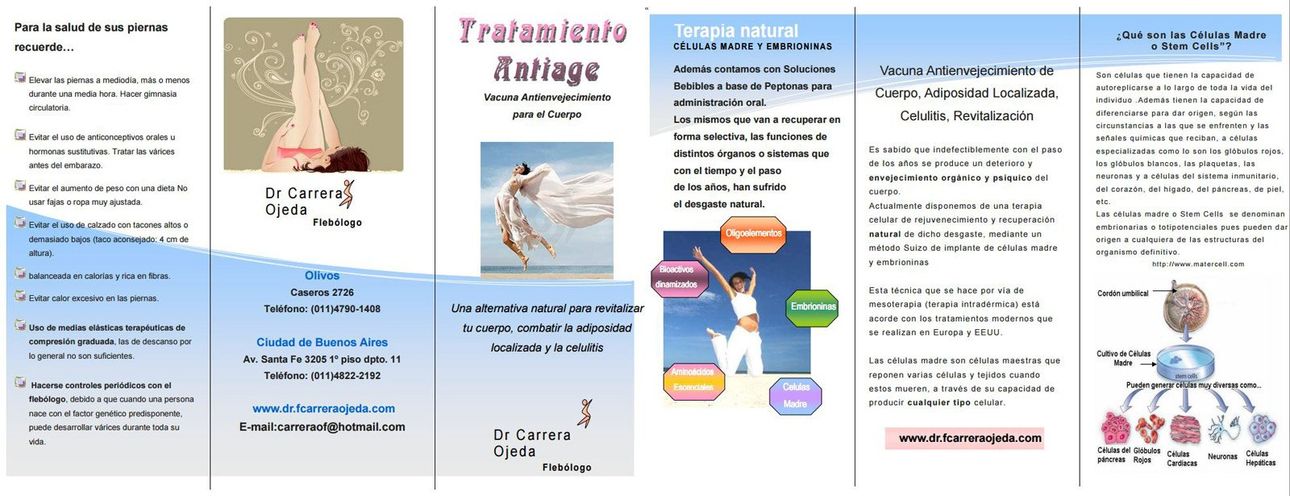

En la siguiente imagen encontrará algunos consejos para el cuidado de sus piernas y de su cuerpo.